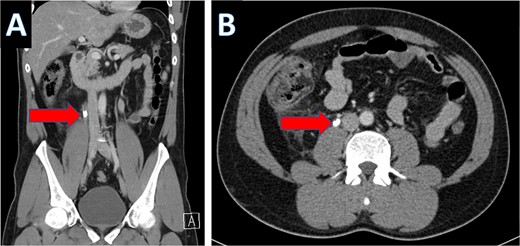

An IV contrast-enhanced CT scan of the abdomen and pelvis revealed an 8-mm proximal to mid-ureteral obstructive stone on the right side (Fig. 1), causing severe hydronephrosis of the right kidney and proximal hydroureter (Fig. 2).

CT scan showing hydronephrosis of the right kidney (A: coronal; B: axial).